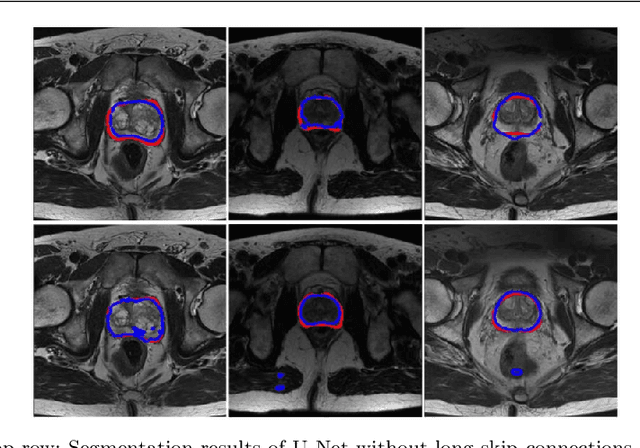

Abstract:Automated medical image segmentation plays an important role in many clinical applications, which however is a very challenging task, due to complex background texture, lack of clear boundary and significant shape and texture variation between images. Many researchers proposed an encoder-decoder architecture with skip connections to combine low-level feature maps from the encoder path with high-level feature maps from the decoder path for automatically segmenting medical images. The skip connections have been shown to be effective in recovering fine-grained details of the target objects and may facilitate the gradient back-propagation. However, not all the feature maps transmitted by those connections contribute positively to the network performance. In this paper, to adaptively select useful information to pass through those skip connections, we propose a novel 3D network with self-supervised function, named selective information passing network (SIP-Net). We evaluate our proposed model on the MICCAI Prostate MR Image Segmentation 2012 Grant Challenge dataset, TCIA Pancreas CT-82 and MICCAI 2017 Liver Tumor Segmentation (LiTS) Challenge dataset. The experimental results across these data sets show that our model achieved improved segmentation results and outperformed other state-of-the-art methods. The source code of this work is available at https://github.com/ahukui/SIPNet.

Abstract:Accurate segmentation of the prostate from magnetic resonance (MR) images provides useful information for prostate cancer diagnosis and treatment. However, automated prostate segmentation from 3D MR images still faces several challenges. For instance, a lack of clear edge between the prostate and other anatomical structures makes it challenging to accurately extract the boundaries. The complex background texture and large variation in size, shape and intensity distribution of the prostate itself make segmentation even further complicated. With deep learning, especially convolutional neural networks (CNNs), emerging as commonly used methods for medical image segmentation, the difficulty in obtaining large number of annotated medical images for training CNNs has become much more pronounced that ever before. Since large-scale dataset is one of the critical components for the success of deep learning, lack of sufficient training data makes it difficult to fully train complex CNNs. To tackle the above challenges, in this paper, we propose a boundary-weighted domain adaptive neural network (BOWDA-Net). To make the network more sensitive to the boundaries during segmentation, a boundary-weighted segmentation loss (BWL) is proposed. Furthermore, an advanced boundary-weighted transfer leaning approach is introduced to address the problem of small medical imaging datasets. We evaluate our proposed model on the publicly available MICCAI 2012 Prostate MR Image Segmentation (PROMISE12) challenge dataset. Our experimental results demonstrate that the proposed model is more sensitive to boundary information and outperformed other state-of-the-art methods.

Abstract:Prostate segmentation from Magnetic Resonance (MR) images plays an important role in image guided interven- tion. However, the lack of clear boundary specifically at the apex and base, and huge variation of shape and texture between the images from different patients make the task very challenging. To overcome these problems, in this paper, we propose a deeply supervised convolutional neural network (CNN) utilizing the convolutional information to accurately segment the prostate from MR images. The proposed model can effectively detect the prostate region with additional deeply supervised layers compared with other approaches. Since some information will be abandoned after convolution, it is necessary to pass the features extracted from early stages to later stages. The experimental results show that significant segmentation accuracy improvement has been achieved by our proposed method compared to other reported approaches.